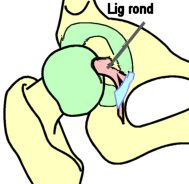

- le ligament de la tête du fémur est une lame (longueur env.

fémorale et se divise en 3 faisceaux au niveau de l'échancrure

termine en ARR de la corne postérieure de l'acétabulum / Moyen

passant sous le ligament transverse de l'acétabulum).

Il empêche l'extraction en cas de luxation de l'articulation.